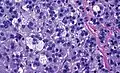

Histopathology

The microscopic histopathology analysis of the tissue samples obtained from the adrenal cortex of individuals presenting with adenoma-associated symptoms such as primary aldestronism (PA) indicates that adenoma cells are relatively larger with different cytoplasm, and increased variation in nuclear size. This indication is based on comparison between the healthy (normal) and affected (adenoma-associated) adrenal cortex tissue samples.

- Adrenocortical adenoma with focal high grade nuclear atypia

- Adrenocortical adenoma with focal necrosis

Adrenocortical adenomas are most commonly distinguished from adrenocortical carcinomas (their malignant counterparts) by the Weiss system,[10] as follows:[11]

High nuclear grade (enlarged, oval to lobated, with coarsely granular to hyperchromatic chromatin and easily discernible, prominent nucleoli)[12] | 1 |

More mitoses than 5/50 high power fields | 1 |

Atypical mitoses | 1 |

Eosinophilic cytoplasm in >75% of tumor cells | 1 |

Diffuse architecture of >33% of tumor | 1 |

Necrosis | 1 |

Venous invasion | 1 |

Sinusoidal invasion (no smooth muscle in wall) | 1 |

Capsular invasion | 1 |

Total score indicates:[11]

- 0-2: Adrenocortical adenoma

- 3: Undetermined

- 4-9: Adrenocortical carcinoma